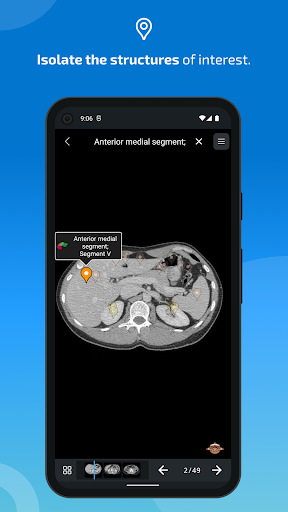

- You can now hide structures one by one (new button inside the description popup) and display them again in the right menu